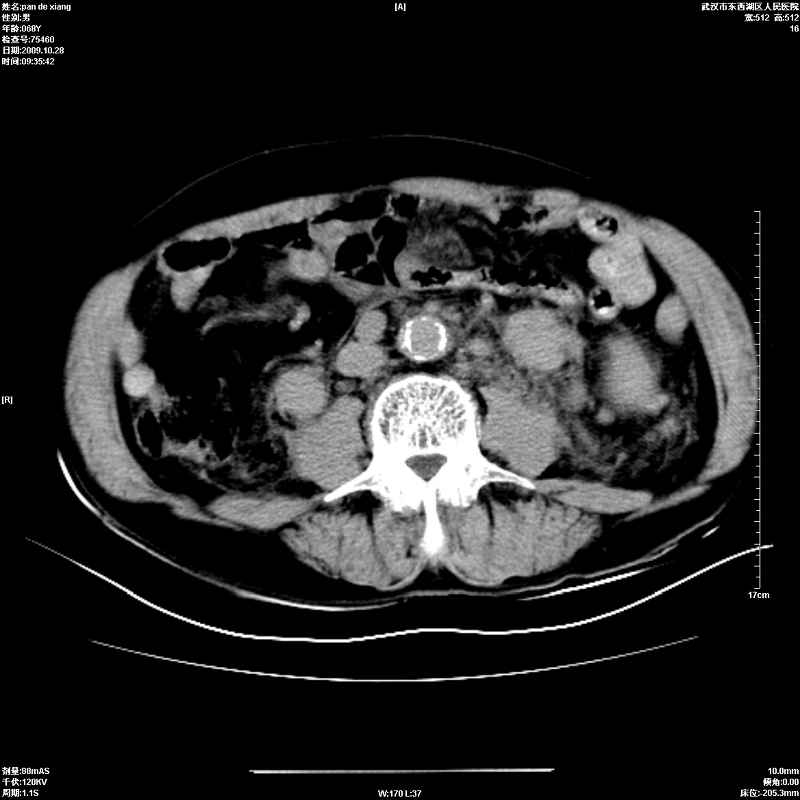

以下是引用杀毒软件在2009-10-28 20:41:00的发言:[br]结合临床考虑---白血病双肾改变或淋巴瘤。

以下是引用zxl51642在2009-10-29 9:59:00的发言:[br]结合临床“单克隆免疫球蛋白血症”,考虑双肾为继发损害并肾功能不全(尿中大量igg及少量iga、igm等大分子免疫球蛋白滤出所致继发损害),椎前软组织肿块为髓外造血。与浆细胞瘤有区别,平扫时有战友说的很清楚。